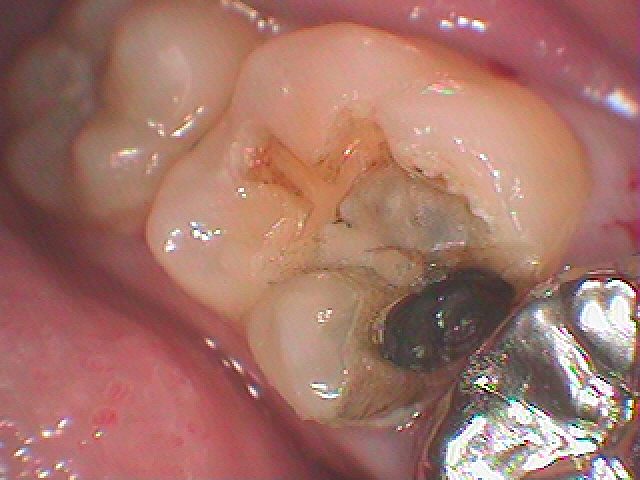

問題の歯になります

中は大きく虫歯になっていました